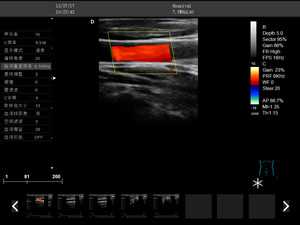

DW-F3

彩色多普勒

全數字成像技術

2.彩色多普勒速度模式

3.能量多普勒模式

4.方向彩色能量多普勒模式

5.脈沖頻譜多普勒模式

6.三同步模式